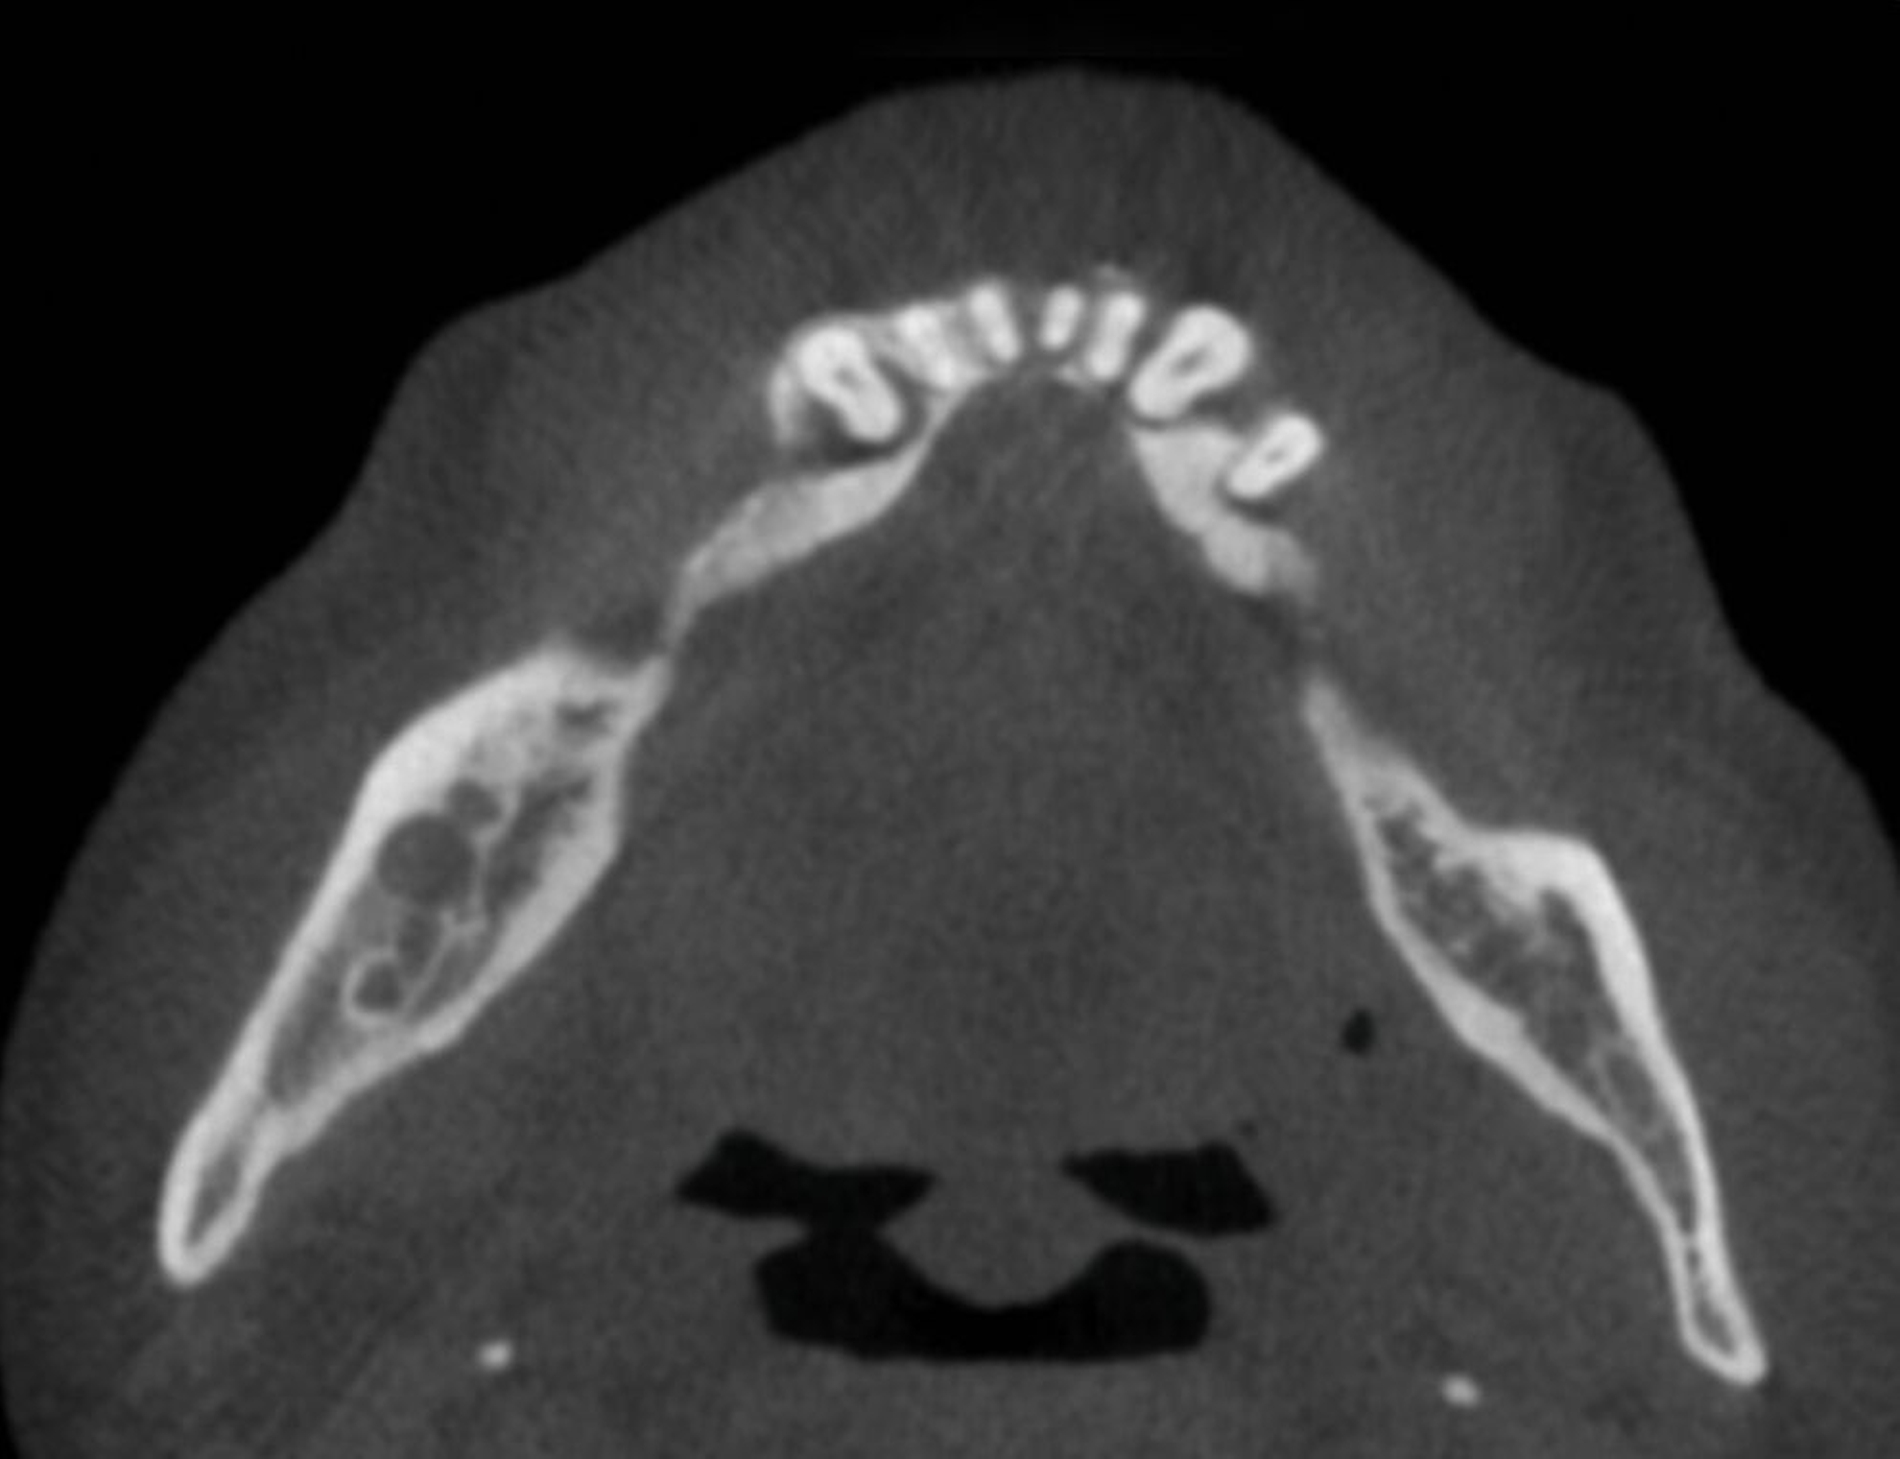

Während sich in den folgenden Jahren vor allem eine rückläufige Läsion mit Verknöcherung des ehemaligen Zystenlumens zeigte, stellte sich der Patient 2024 mit einer plötzlich progredienten Hypästhesie des rechten Nervus alveolaris inferior vor. Bei Verdacht auf Vorliegen eines Rezidivs des bekannten Ameloblastoms erfolgte eine Panoramaschichtaufnahme (Abbildung 1), die den Verdacht erhärtete. Im anschließend folgenden DVT zeigten sich multiple, kreisförmig-zystische Aufhellungen die sich vom Kieferwinkel bis regio 45 erstreckten (Abbildung 2).